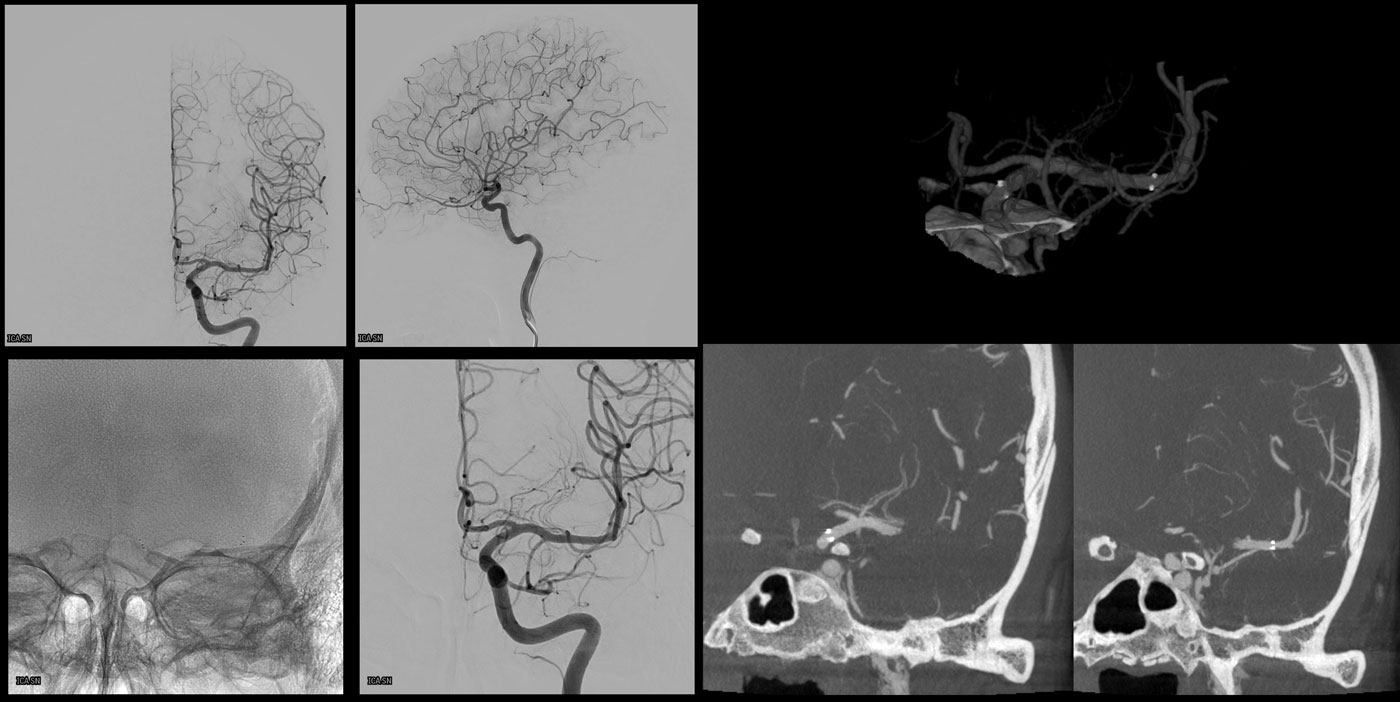

VASO-CT post

24h CT-scan

24h CTA and CTP

6 months DSA follow up